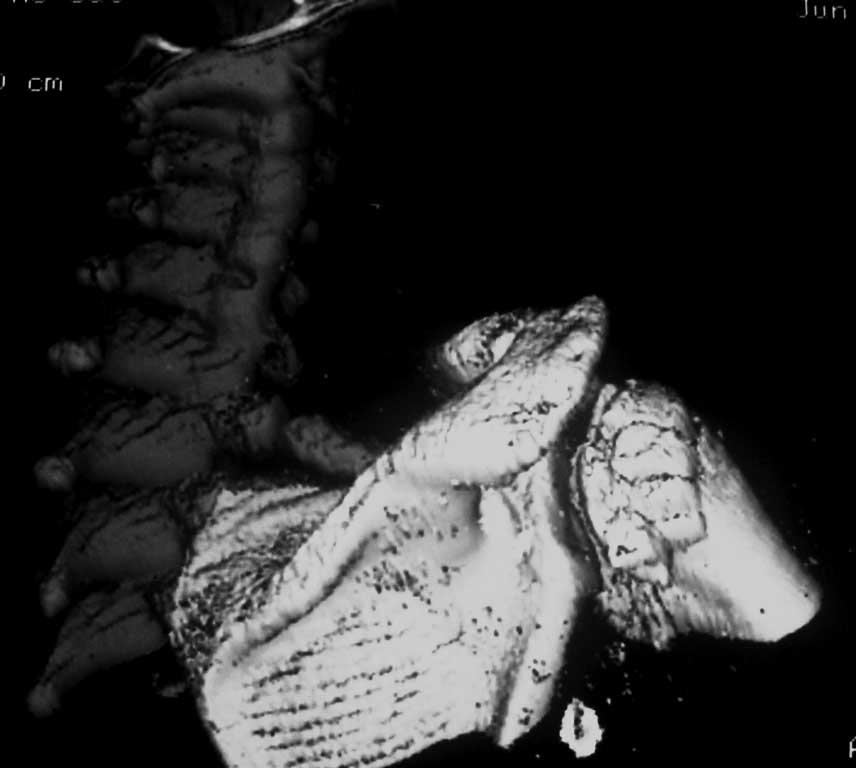

Вложение не в текстовом формате было извлечено…

Имя     : 3Д.JPG

Тип     : image/jpg

Размер  : 56687 байтов

Описание: отсутствует

Url     : http://weborto.net:8080/pipermail/ortho/attachments/20120609/f6e7d42f/attachment-0005.jpg